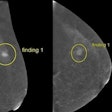

Studies shed light on false-negative DBT findings